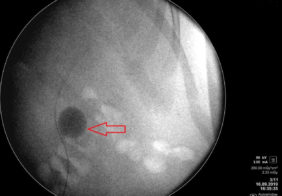

Дроблення коралоподібного каменя через 5 мм. прокол на шкірі

Лікування коралоподібного каменю 1 ступеню право, нирки